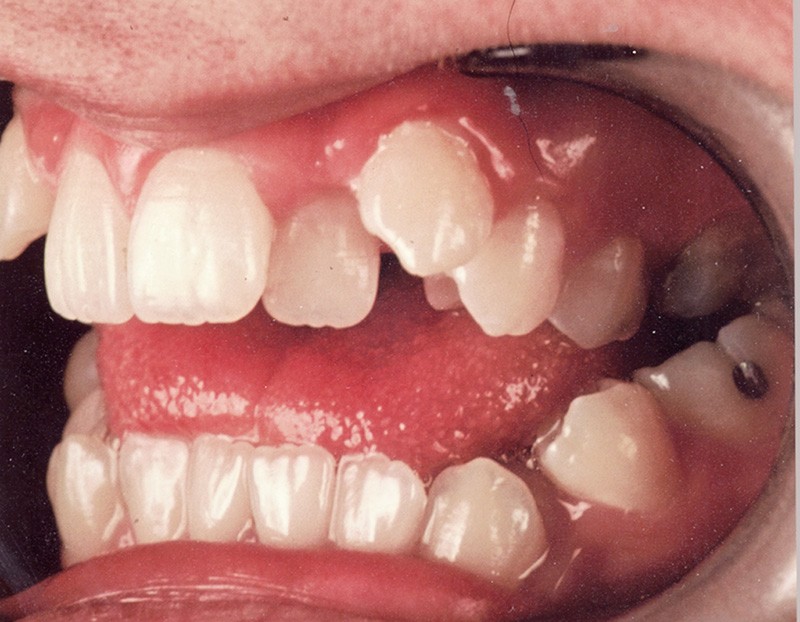

Au niveau squelettique, elle présente une classe I associée à une endognathie maxillaire et une hyperdivergence mandibulaire majeure liée à un excès de croissance alvéolaire verticale postérieure maxillaire et une inclinaison mandibulaire très marquée (fig. 1 et 3).

Sur le plan occlusal et dentaire, on observe une classe I molaire, une occlusion transversale en bout à bout à droite et inversée à gauche et une béance antérieure sévère s’étendant jusqu’aux molaires. Un encombrement est présent aux deux arcades avec des dystopies canines importantes (fig. 2).